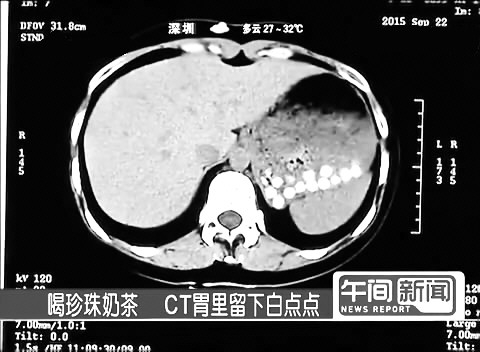

摘要:近日,一张胃部CT片在微信朋友圈疯传。透过CT图片,可以清楚看见胃部的白色小点,就像一颗颗小石头一样。图片下面配文:“珍珠奶茶中的珍珠,据说这些珍珠都是用塑料做的(未证实),真的好恐怖,同事说十二指肠里面也有,都引起梗阻,胃下垂了!”

当记者喝下大杯珍珠奶茶半小时后进行CT监测,结果和网上的CT图片如出一辙:不大的胃部排着二十多颗边际清晰的白色圆点,这个结果让影像科的医生大呼吃惊,怀疑珍珠里有非常黏稠的物质。

浙大一院急诊科医生宁建文在接受相关媒体采访时表示,昨晚也看到了朋友圈里的这则图片。他认为,这张CT图应该是按照横切位置拍的,CT图左边是肝脏,右边是胃,胃里有几十颗密密麻麻的小白点,非常明显。

“从CT上看,这些小白点的大小和在CT扫描下呈现的密度,的确和珍珠奶茶里的珍珠很像。但奇怪的是,CT显示这些小白点的形状都呈圆形。”

宁建文医生分析认为,光从CT片看,无论如何也得不出这些珍珠奶茶与塑料之间的联系。因为珍珠奶茶里的珍珠如果用的是糯米、葛粉等黏性很强的原 材料,比较难消化,如果不经细嚼慢咽吞到胃里,在CT扫描下也是有可能会呈现出图片中的小白点。之前他们接诊过一些吞食糯米糕点引发胃部不适而来医院就诊 的患者,拍出来的CT就会有类似的白点,但大小和形状不太一样。